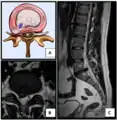

Intradural disc herniation is a rare form of disc herniation with an incidence of 0.2–2.2%. Pre-operative imaging can be helpful for diagnosis, but intra-operative findings are required for confirmation.[26]

- Click images to see larger versions

Lumbar disc lesions, classification

Normal situation and spinal disc herniation in cervical vertebrae

Illustration depicting herniated disc and spinal nerve compression

Nucleus herniating through tear in annulus (with MRI)[9]

Illustration showing disc degeneration, prolapse, extrusion and sequestration